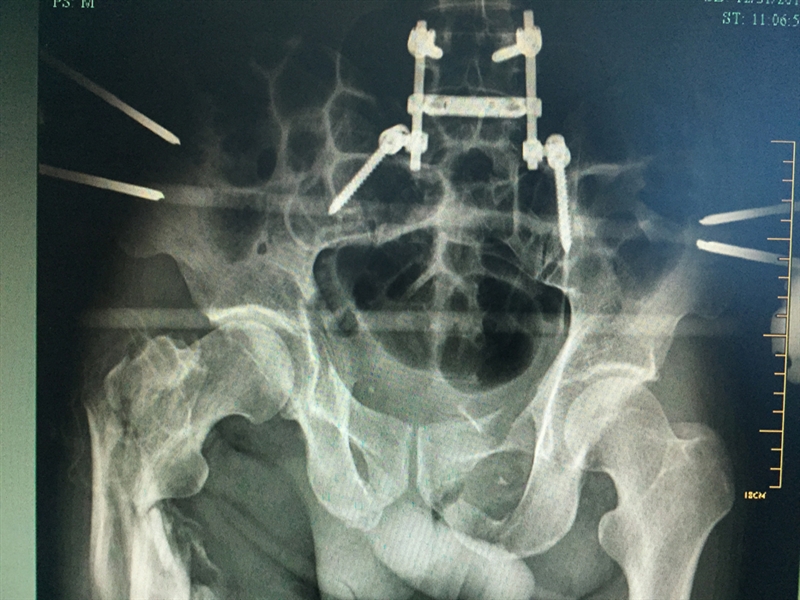

??? 說起張成的經(jīng)歷,讓人唏噓不已。2015年12月4日,46歲的張成不慎從四層高樓墜落,當場不省人事。家人立即將張成送入當?shù)蒯t(yī)院搶救,經(jīng)檢查發(fā)現(xiàn)張成血氣胸,創(chuàng)傷性濕肺,全身多處骨折,光肋骨就有11根骨折,右側(cè)股骨骨折,右側(cè)肱骨下段粉碎性骨折,最嚴重的是還有脾破裂,骨盆骨折和胸椎骨折。因傷勢嚴重,當?shù)蒯t(yī)院建議家屬將張成轉(zhuǎn)到上一級醫(yī)院。

患者入院時的X影像

??? 當天,張成被轉(zhuǎn)入衢州市人民醫(yī)院救治。到達衢州市人民醫(yī)院之后,緊張的生命接力就開始了,傷情相當嚴重,張成生命垂危,重癥醫(yī)學科(ICU)醫(yī)護團隊立即投入戰(zhàn)斗,進行搶救;生命體征一轉(zhuǎn)平穩(wěn),待命的普外科、麻醉科、手術室醫(yī)護人員馬上進行脾臟切除術;最后把接力棒交給了骨科,方智敏主任會診后深知這是一個艱巨的任務,隨即帶領診療組探討治療方案,最終制定了詳細的診療計劃,前后對患者進行了三次大手術……從12月4日至12月31日,短短一個月的時間,張成就接受了五次手術。

??? 患者術后的部分X影像